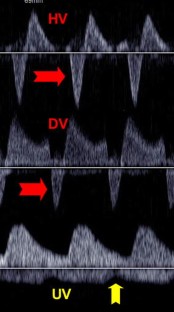

A Fetus With Hypoplastic Left Heart Syndrome and Tricuspid Stenosis With Evolving Hydrops Fetalis

Hypoplastic left heart syndrome (HLHS) is a severe congenital heart defect that results in death if not treated shortly after birth. In approximately 60 to 70% of cases, HLHS can be detected prenatally and generally is well tolerated due to the presence of the foramen ovale and ductus arteriosus, which allow for blood to bypass the left side of the heart but still provide adequate blood flow to the systemic circulation. A rare case of HLHS involving a fetus with tricuspid valve stenosis, abnormal venous Doppler findings, and hydrops is reported.